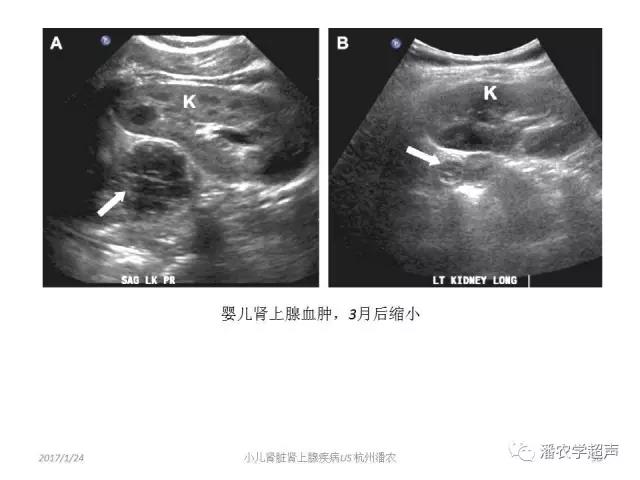

肾上腺血肿